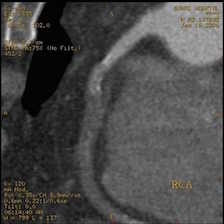

一部の症例以外では、従来の心臓カテーテル検査なしに血管狭窄の評価が可能であり、万が一、心筋梗塞になられた場合でも治療後の経過観察の心臓カテーテル検査は不要となります。

①安定した心臓撮影 : 心臓を5秒にて撮影(従来のマルチスライスCTでは約20秒間撮影)